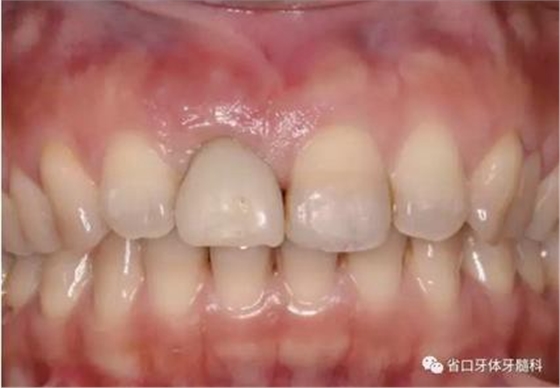

1.?病例簡介 43歲女性患者,主拆:右上前牙松動不適數(shù)日要求修復(fù)。現(xiàn)病史:患者數(shù)年前右上前牙因“齲壞”于外院行根管治療(具體不詳),數(shù)日前牙冠松動不適,現(xiàn)覺影響咀嚼及美觀,遂來我院要求進(jìn)一步診治。否認(rèn)高血壓、心臟病等重大疾病,否認(rèn)結(jié)核、肝炎等傳染病史,否認(rèn)手 術(shù)、輸血史等,未發(fā)現(xiàn)藥物過敏。無吸煙習(xí)慣。臨床檢查:口外觀顏面基 本對稱,皮膚無紅腫破潰,顳下頜關(guān)節(jié)區(qū)無彈響、雜音、壓痛,開口度約 37mm,開口型“↓”,頜下、刻下和頸部未及腫大淋巴結(jié)。中位笑線??趦?nèi)檢查,口腔衛(wèi)生可,色素(+),BOP(-),PD=2mm,上頜右側(cè)中切 牙冠部變色,冠根折斷至齦下3mm,叩不適,松動Ⅱ°~Ⅲ°。牙齦稍紅, 齦緣水平及齦乳頭高度可,屬于中厚齦生物型,附著齦寬度約5mm,唇系帶附著可。上頜右側(cè)中切牙缺牙間隙與對側(cè)同名牙一致,約>7mm,修復(fù)空 間良好。與對頜牙覆合覆蓋正常。MCT檢查示上頜右側(cè)中切牙冠根折斷至骨 下,根管內(nèi)見充填物,根充不全,根尖見陰影,大小約3mm×3mm。牙槽窩根方可用骨量可,唇側(cè)骨壁完整,冠方骨壁厚度約1mm。

圖1 術(shù)前口內(nèi)照

圖2 術(shù)前口內(nèi)照

圖3 術(shù)前口內(nèi)照